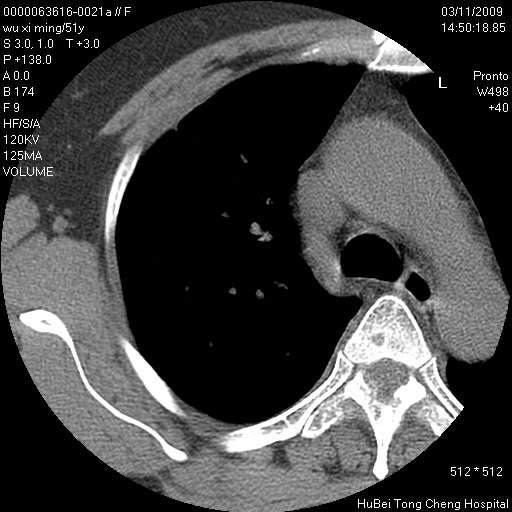

患者 女,51岁。因“胆囊炎,胆囊结石”,行常规术前胸部x线检查发现:右上肺结节病灶,建议行进一步检查。患者无咳嗽、咳痰及咯血等呼吸道症状,近期出现背部疼痛不适。

胸部ct轴位平扫(层厚10mm,螺距1.5,重建间隔10mm;部分层面:层厚3mm,螺距1.0,重建间隔3mm),图像如下:

右肺周围型肺癌伴肺内转移信胸椎转移

1、周围型肺癌。(毛刺正、血管束集征,分叶。)

集束征,胸膜牽拉征,毛刺,淺分葉高度提示ca.

右肺周围型肺癌伴肺内转移及胸椎转移。已无手术机会。